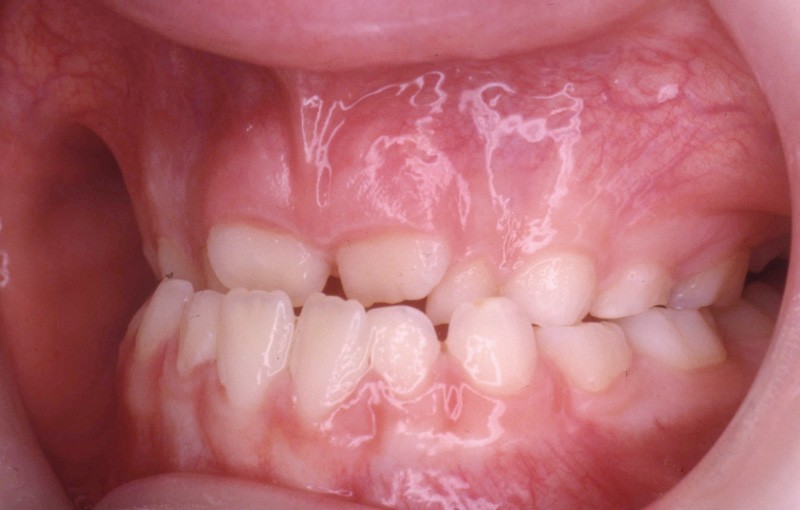

L’examen de la denture (fig. 3 à 5) montre :

• dans le sens antéro-postérieur, des relations molaires et canines de type classe III d’Angle et une inversion des rapports incisifs,

• dans le sens transversal, une endomaxillie bilatérale prédominante dans la région canine.